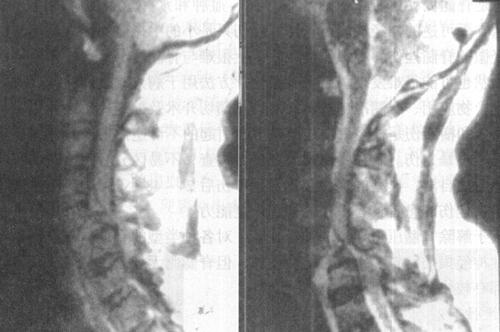

急性脊髓创伤常由于脊柱结构破坏(图7-12a和b),如撕裂伤、横断伤或严重挫伤,也可由内在的可逆性损伤如震荡或轻微挫伤引起,还可以由外来的可逆损伤如脊髓受压引起(图7-13)。按损伤程度分为脊髓震荡伤、脊髓挫伤、脊髓撕裂伤和横断伤。

图7-12a 颈段脊髓横断性损伤。颈椎正侧位片:C5以上前脱位,该水平段椎管狭窄,可推测脊髓受压迫

图7-12b MRI矢状面T1WI可见颈髓在C5水平明显受压,椎体前缘和椎管内可见中等偏高信号,局部颈髓可见斑点状高信号;12WI被压迫的脊髓亦见高信号出血灶,脊椎前方前纵韧带下血肿,呈高信号

图7-13 胸椎压缩性骨折伴脊髓压迫:T1WI和T2WI示T10压缩性骨折后凸畸形,脊髓压迫